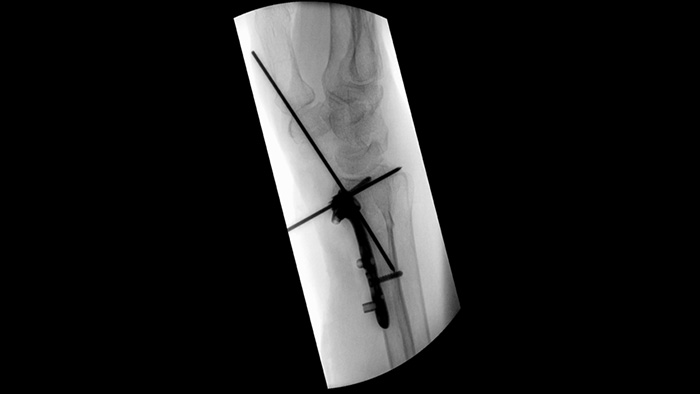

MetalSmart automatically excludes metal artifacts caused by metal implants to provide higher image quality and efficient dose control during orthopedic procedures and patients with metal implants, compared to systems without metal exclusion. BodySmart promotes first-time-right imaging and dose efficiency by automatically adapting the measuring field to the area of interest.

When setting pedicle screws for a spinal fusion or fracture repair, reducing technical distractions and discussions can help surgical teams remain focused on the patient. With Unify workflow’s navigation aids, surgical teams experienced smoother interactions and less miscommunication in a usability study.1